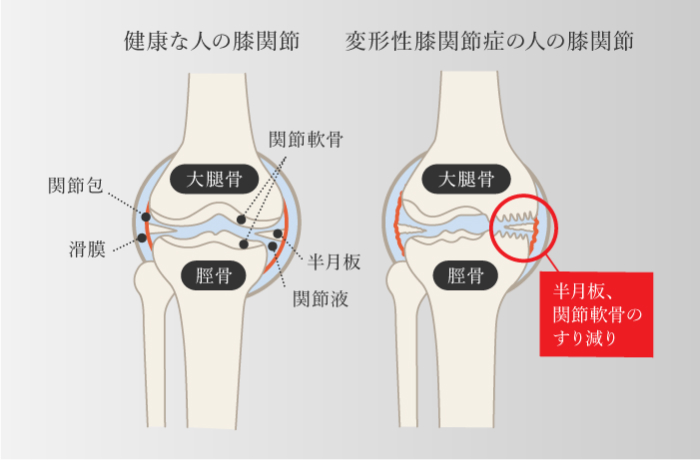

変形性膝関節症

関節軟骨の老化が原因になることが多く、肥満なども関与している。また骨折、靱帯や半月板損傷などの外傷、化膿性関節炎などの感染の後遺症としても発症する可能性がある。 関節軟骨が年齢とともに弾力性を失い、使い過ぎることによってすり減り、関節が変形する。

半月板損傷

半月板は大腿骨と脛骨の間の三日月型をした組織で、膝関節のクッションの役割を果たしている。ジャンプ時の着地や方向転換など荷重された状態で膝を強く捻ったり、キック動作で膝を急激に伸ばす動作やその反復で損傷する。